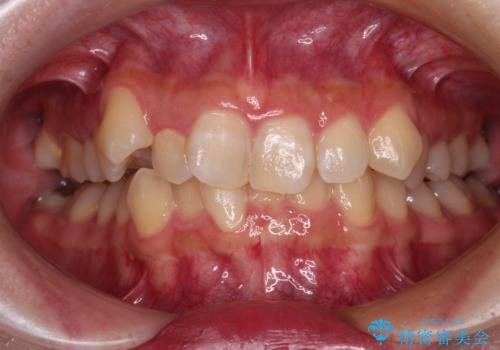

前歯のクロスバイトをインビザラインで矯正治療

- 前歯のデコボコとクロスバイトを気にして来院された患者様です。

前歯を早く整えたいとの希望があったので、ワイヤー矯正にて短期間でクロスバイトを解消し、その後インビザラインにて整えることとしました。